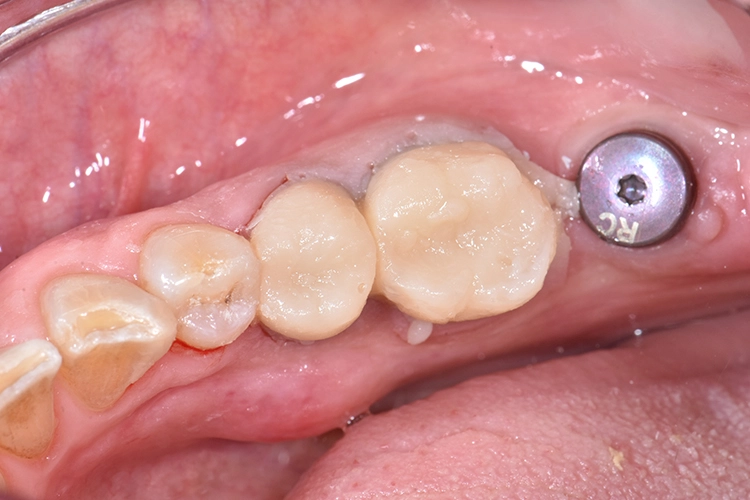

Bilder: Dr. Lampson / HannkerIm vorliegenden Fall stellte sich eine Patientin zur Behandlung vor (Abb. 1). An Position des fehlenden Zahnes 47 wurde ein Implantat auf Knochenniveau gesetzt. Darüber hinaus galt es, die insuffizienten Kronen auf den Zähnen 45 und 46 zu erneuern.

Bilder: Dr. Lampson / HannkerVor Beginn der Behandlung stand die Farbtonbestimmung (Abb. 4). Alte Kronen sowie Karies wurden entfernt, um anschließend mit Gænial® Universal Injectable (GC) den Stumpf aufzubauen und mit einer Hohlkehle zu präparieren (Abb. 5). Zur exakten Übertragung der Implantatposition an Position 47 erfolgte die Abformung mittels Pick-up-Technik.